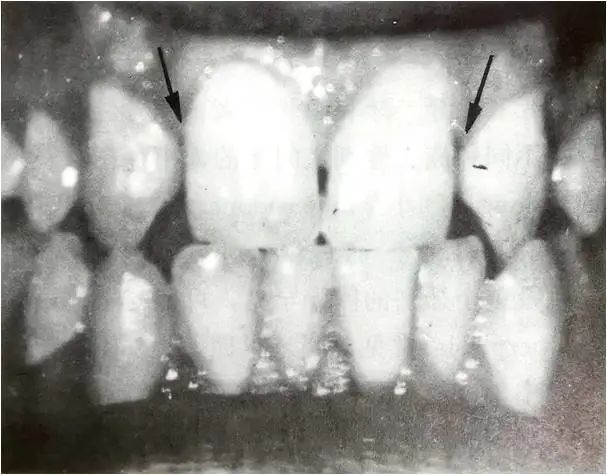

除智齿外,较易缺少的牙齿是上颌侧切牙,就是紧挨着正中门牙、和正中门牙相似但个头较小的那颗牙齿。侧切牙可以是双侧缺失,也可以是单侧缺失。后一种情况必然使得牙列分布呈现不对称性,最终造成牙列中线发生偏移,即左右门牙之间的牙缝偏向一侧。

箭头所示为双侧上颌侧切牙缺失